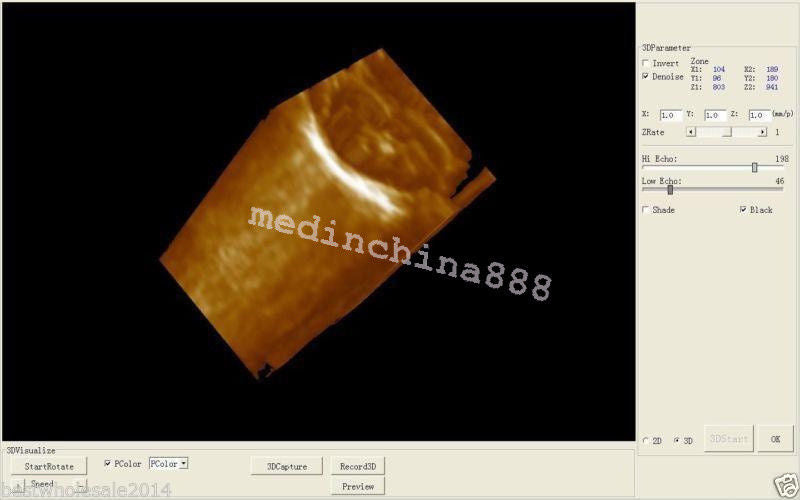

The Laptop LCD Digital 10.1-Inch Ultrasound Scanner is designed for high-quality imaging. This portable device offers detailed visuals, allowing healthcare professionals to deliver accurate diagnoses effortlessly. Equipped with both convex and transvaginal probes, it enhances versatility in various medical procedures. Its compact design ensures that you can carry it easily between locations, making it an essential tool for any medical practice. The user-friendly interface further simplifies operation, so you can focus on patient care without unnecessary distractions.